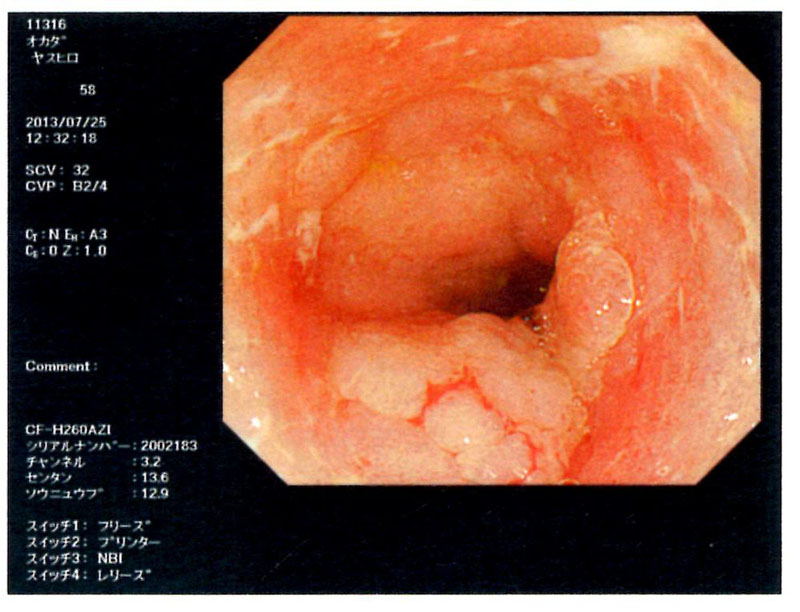

4.潰瘍性大腸炎(大腸全摘手術2013年11月28)

| 内視鏡検査(大腸カメラ) |

がん予備群ポリープ |